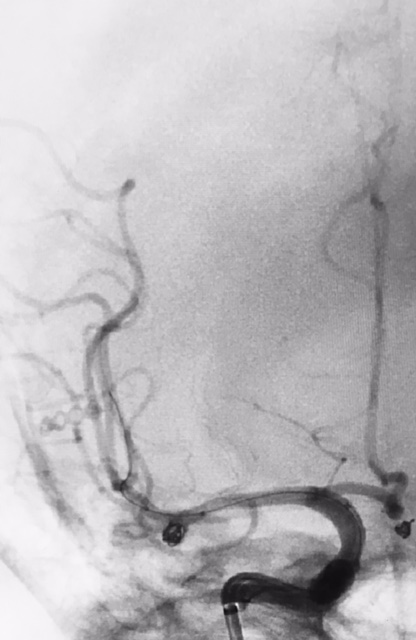

Tratamento de aneurisma cerebral com auxílio de balão duplo lumém e neurostent LEO